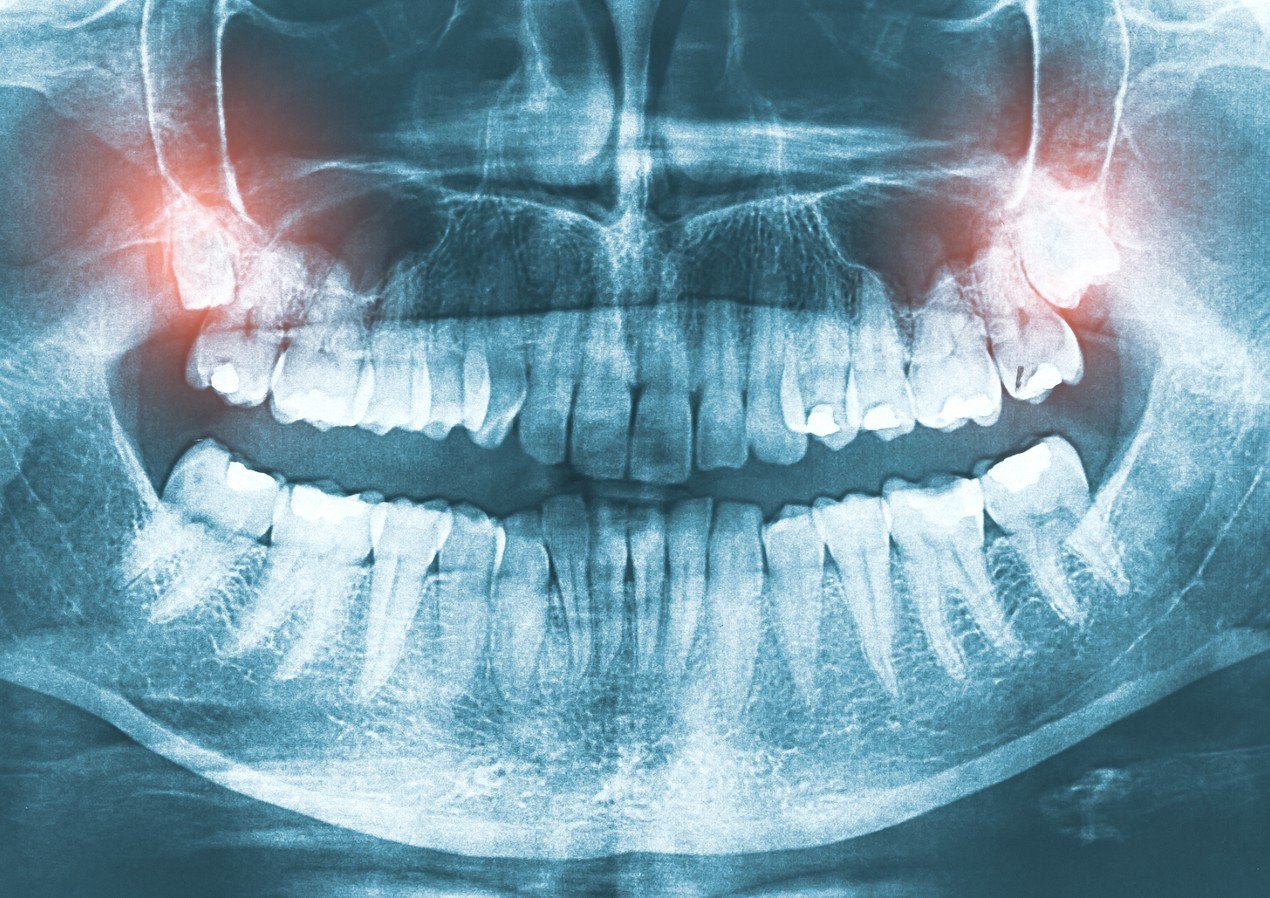

Prior to the extraction your dentist will take an X-ray to assess the shape and length of the roots. Your tooth, jawbone and gums will be numbed a local anesthetic.

Wisdom teeth become a problem as they begin to grow most commonly in patients that do not have enough space at the rear of the jaw to fit them. If this happens, the teeth become wedged in behind the tooth in front (impacted). Impacted wisdom teeth can cause a variety of problems including infection, pain, damage to nearby molars, and food packing which can then lead to decay.